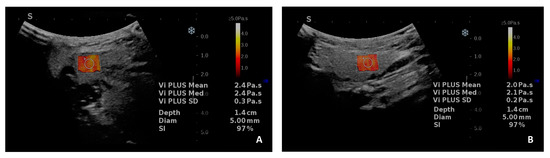

- Muntean, D.; Lenghel, M.; Ciurea, A.; Dudea, S. Viscosity Plane-wave UltraSound (ViPLUS) in the assessment of parotid and submandibular glands in healthy subjects—Preliminary results. Med. Ultrason. 2022, 24, 300–304. [Google Scholar] [CrossRef]

- Muntean, D.D.; Lenghel, M.L.; Petea-Balea, D.R.; Ciurea, A.I.; Solomon, C.; Dudea, S.M. Functional Evaluation of Major Salivary Glands Using Viscosity PLUS and 2D Shear-Wave PLUS Elastography Techniques in Healthy Subjects-A Pilot Study. Diagnostics 2022, 12, 1963. [Google Scholar] [CrossRef]